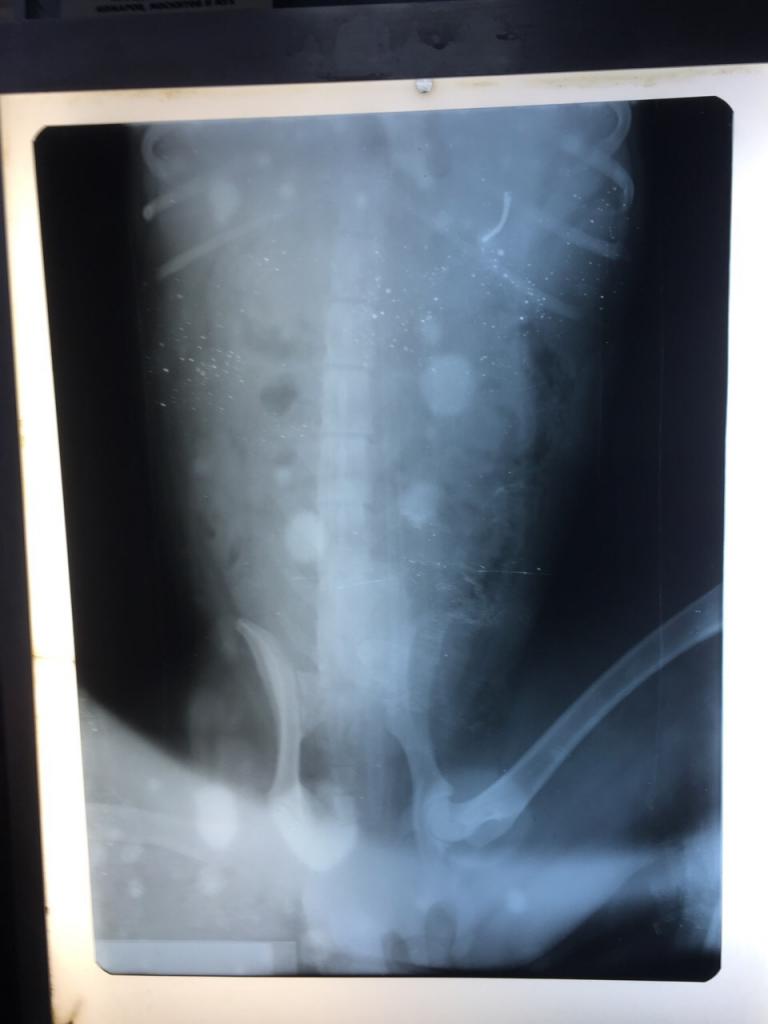

Вчерашний диагноз к сожалению был ошибочный, перелома у него нет. Но проблема как и предполагалось намного серьезнее. В позвоночнике нашли пулю возможно именно она стала причиной повреждения спинного мозга, возможно сопутствовал удар который усугубил положение, наверняка никто не может знать.

Что делать... Как сказал врач нужно делать КТ (компьютерную томографию) Что бы понять насколько серьезные повреждения и только ли проблема в пуле, может есть еще повреждения, и насколько сильно поврежден спинной мозг. После этого нужно делать операцию.